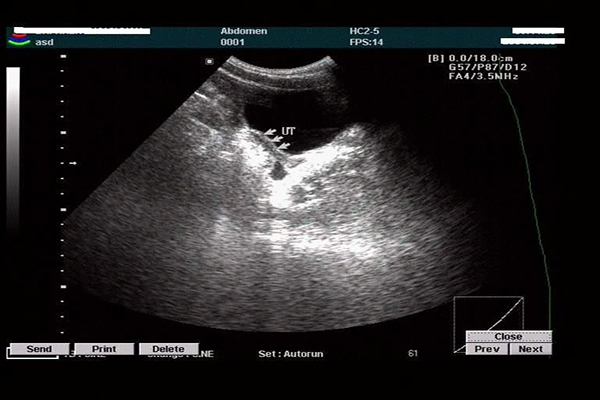

始基子宫和幼稚子宫都属于子宫畸形的表现,而且经常有人把始基子宫和幼稚子宫混淆,但其实这二者虽然十分相似,但是有着较大的差异,这二者从宫腔结构,表现症状,以及超声..

有些女性朋友在结婚后长时间备孕都没有动静,到医院检查才知道是幼稚型子宫。幼稚子宫其实就是指子宫发育不良。它相对比正常子宫要小,在B超的诊断上子宫的三个径线加起来..